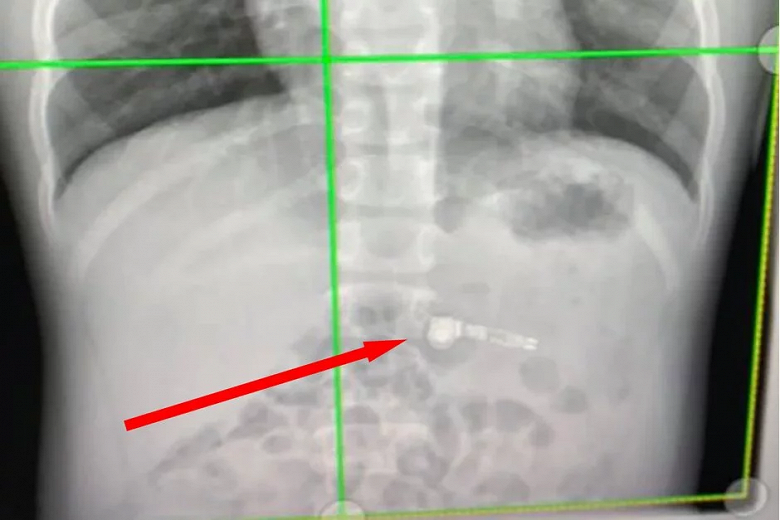

Киара Страуд (Kiara Stroud), мать ребенка, рассказала, что мальчик просто проглотил один из наушников. Она говорит, что и представить себе не могла подобного развития событий. Теперь она считает своим долгом предупредить других родителей о том, что подобные миниатюрные гаджеты могут быть действительно опасными в руках детей этого возраста.

Мама рассказывает, что ее ребенок просто держал один наушник во рту за длинную часть, а потом проглотил, при этом она не успела отреагировать. Специалисты в отделе охраны здоровья детей Атланты были озадачены этим обстоятельством, обнаружив на рентгеновском снимке один из наушников AirPod.